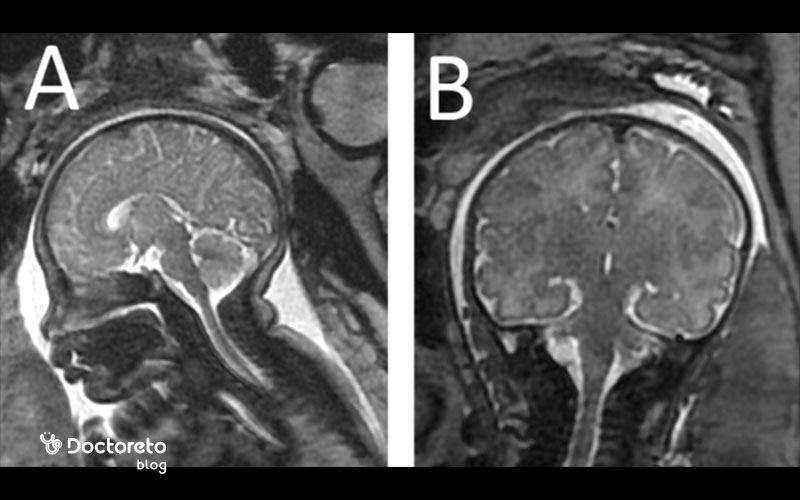

حتی در صورت تشخیص کوچکی سر جنین در سونوگرافی، پزشک بعد از تولد بررسیهای مورد نیاز را انجام میدهد تا بتواند به صورت دقیقتر، میکروسفالی بودن نوزاد را تشخیص دهد. MRI و آزمایش ژنتیک میتوانند میزان تشخیص میکروسفالی را بهبود ببخشند و بنابراین به عنوان بخشی از بررسیهای اولیه تشخیصی، توصیه میشوند.

میکروسفالی را میتوان در رحم با استفاده از اسکن اولتراسوند تشخیص داد، تکنیکی که امواج صوتی با فرکانس بالا و فناوری رایانه را برای تولید تصاویر تشخیصی از رگهای خونی، اندامها و بافتهای در حال رشد نوزاد ترکیب میکند. با این حال، میکروسفالی معمولاً با این تکنیک تا سه ماهه سوم قابل مشاهده نیست و برای تشخیص میکروسفالی در سونوگرافی، حداقل باید تا اواخر سه ماهه دوم بارداری صبر کرد. پزشک معمولاً در تصاویر اولتراسوند به دنبال شواهدی از سر غیرطبیعی کوچک میگردد. حتی در صورتی که مشاهدات پزشک در تصاویر سونوگرافی، کوچک بودن سر نوزاد را نشان دهد، هنوز هم نمیتوان تا زمان تولد و انجام معاینات دقیق فیزیکی، میکروسفالی بودن جنین را تشخیص داد.